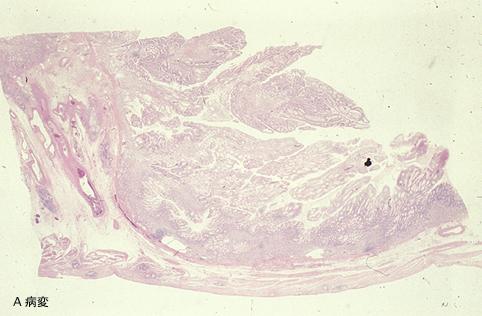

疾病(病理主体)的分类肿瘤样病变/幼年性息肉病

部位(按器官分)胃(部位)/胃角

检查方法病理切片(微观)